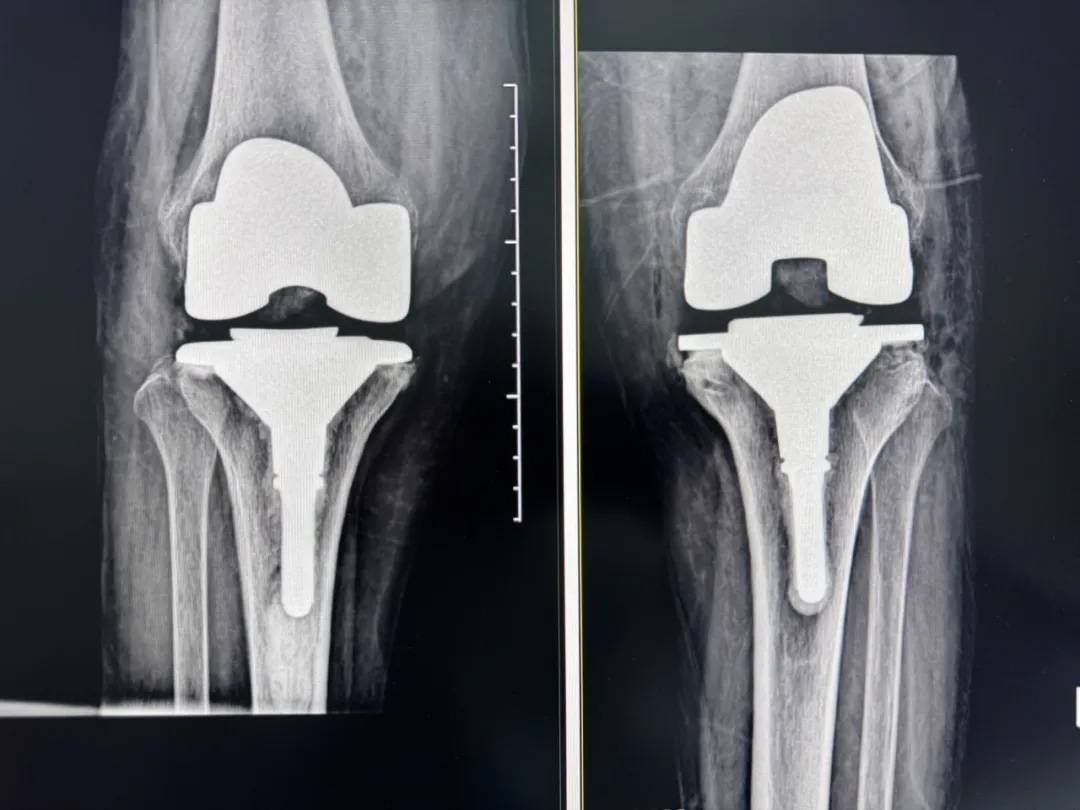

術(shù)前:AI通過CT掃描生成毫米級膝關(guān)節(jié)三維模型,為假體安裝設(shè)計(jì)出誤差小于1毫米的精準(zhǔn)方案 術(shù)中:智能導(dǎo)航系統(tǒng)如同"透視眼",引導(dǎo)醫(yī)生避開密集的神經(jīng)血管網(wǎng),截骨更精準(zhǔn),出血僅100ml 術(shù)后:當(dāng)天鄭阿婆即開始抬腿的康復(fù)訓(xùn)練,24小時(shí)內(nèi)扶助行器下地行走,三天后已能在病房走廊獨(dú)立行走,完成洗漱用餐 兩周后健步出院時(shí),女兒含淚感慨“之前擔(dān)心她年紀(jì)大扛不住手術(shù),沒想到恢復(fù)這么快!現(xiàn)在每天散步比我還精神。知道技術(shù)這么先進(jìn),真該早點(diǎn)來!”

"這就像給傳統(tǒng)手術(shù)裝上了自動(dòng)駕駛系統(tǒng)。"主刀醫(yī)生羅軍副院長用生動(dòng)比喻解析技術(shù)突破。AI不僅實(shí)現(xiàn)假體“量身定制”,使用壽命可達(dá)20年以上,更通過三維路徑規(guī)劃將康復(fù)周期壓縮,實(shí)現(xiàn)術(shù)后24小時(shí)下地,2周回歸正常生活。同時(shí),AI會(huì)避開重要組織,具有出血少、感染風(fēng)險(xiǎn)低的特點(diǎn)。專家特別提醒,當(dāng)出現(xiàn)夜間持續(xù)性關(guān)節(jié)疼痛、步行能力低于10分鐘或關(guān)節(jié)畸形時(shí),應(yīng)及時(shí)就醫(yī)評估,"別等到關(guān)節(jié)'報(bào)廢'才手術(shù)"。